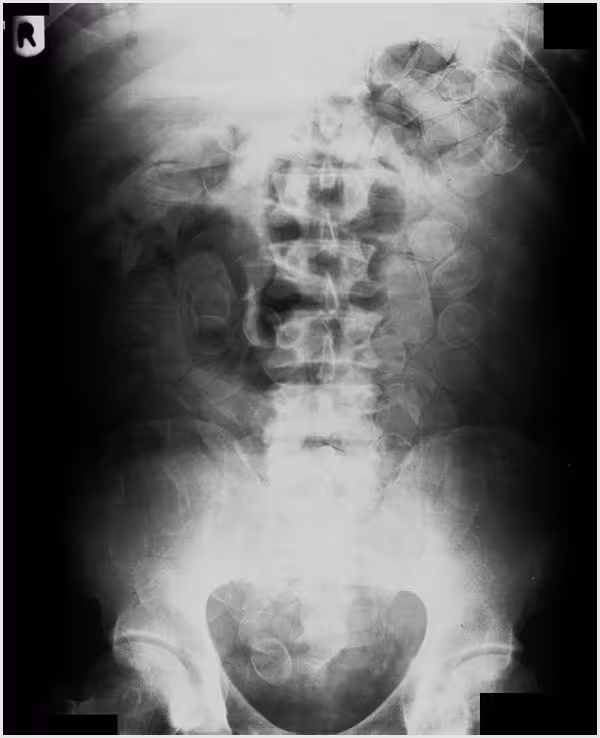

X-ray of an abdomen piled up with cocaine